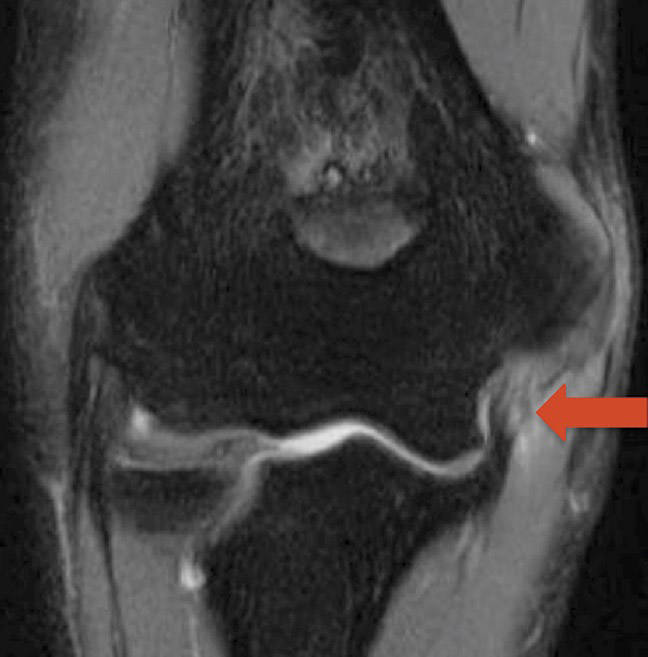

• Magnetic resonance imaging (MRI) scans. An MRI can better show the soft tissues, like the ulnar collateral ligament. Often, an MRI arthrogram is ordered, in which a special dye is injected into your elbow joint to help the doctor better see ligament tears, including small partial tears. An MRI can also show if the ligament is torn from the arm bone (humerus), from the forearm bone (ulna), or at the middle of the tendon. When the tear occurs at the ulna, it is less likely to heal on its own.

MRI image of the elbow showing a complete tear of the ulnar collateral ligament (red arrow).

Reproduced from Desai N, Vance DD, Rosenwasser MP, Ahmad CS. Artistic Gymnastics Injuries; Epidemiology, Evaluation, and Treatment. J Am Acad Orthop Surg 2019; 27(13): 459-467.